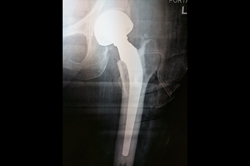

Total Hip Replacement - THR